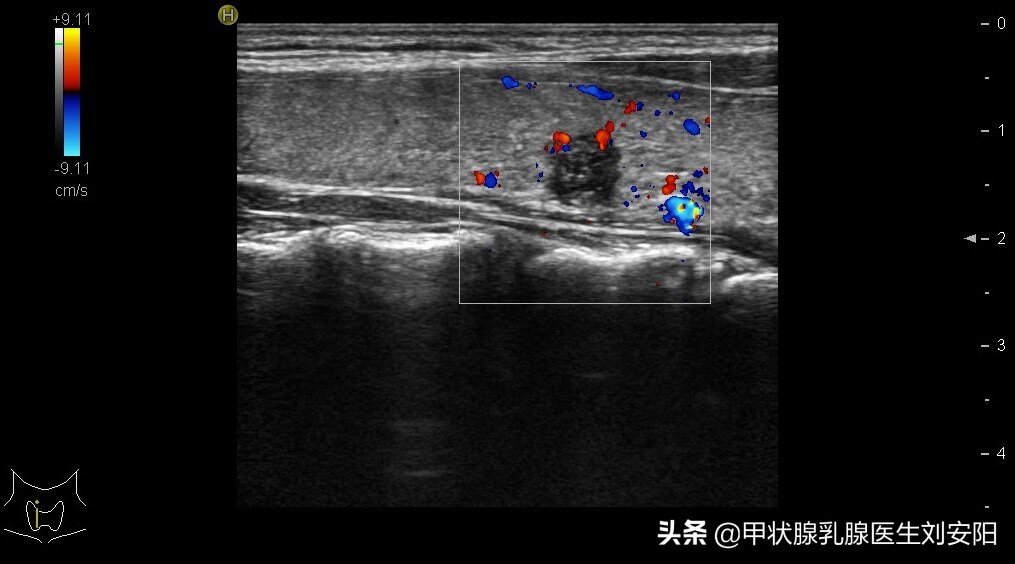

先简单介绍一个病例:患者30岁女性,超声发现右侧甲状腺8mm低回声结节,纵横比>1,可见点状强回声,TIRADS 5类。术前多次彩超均未发现颈部可疑淋巴结。故行甲状腺右叶加峡部切除+预防性右侧中央区(VI区)淋巴结清扫。术后病理:甲状腺乳头状癌,右VI区淋巴结8/11(清扫11枚淋巴结中有8枚可见癌转移)。患者术后2周拿到病理报告后就诊询问:纠结要不要切掉另一侧甲状腺,后加做碘131呢?